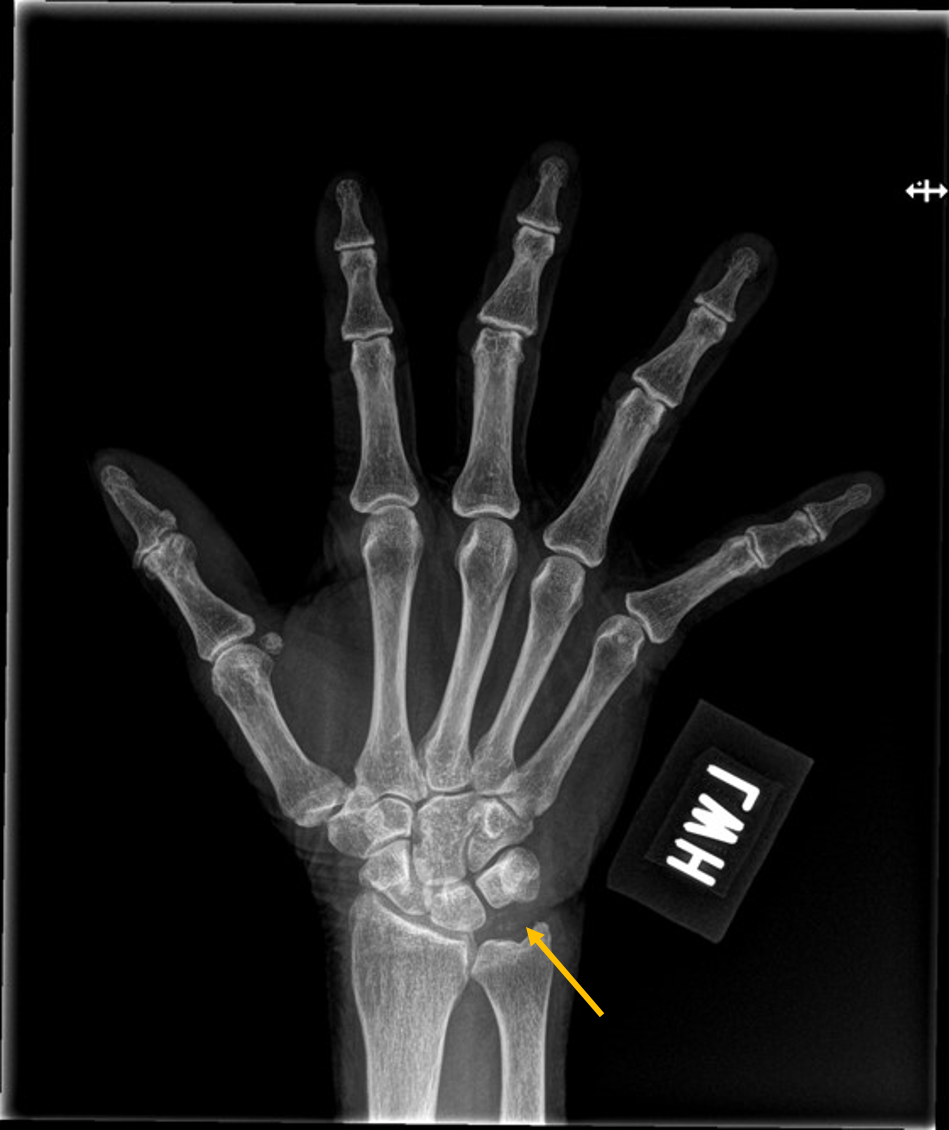

X ray image showed chondrocalcinosis over triangular fibrocartilage complex (TFCC) of right wirst (yellow arrow in Picture 2) and right knee (Picture 3). Asymmetrical joint space narrowing with spur formation (white arrow in Picture 4) of right knee was seen, compatible with OA change. No fracture or joint erosion seen over right elbow. (Picture 5).

Picture 2 Right Wrist